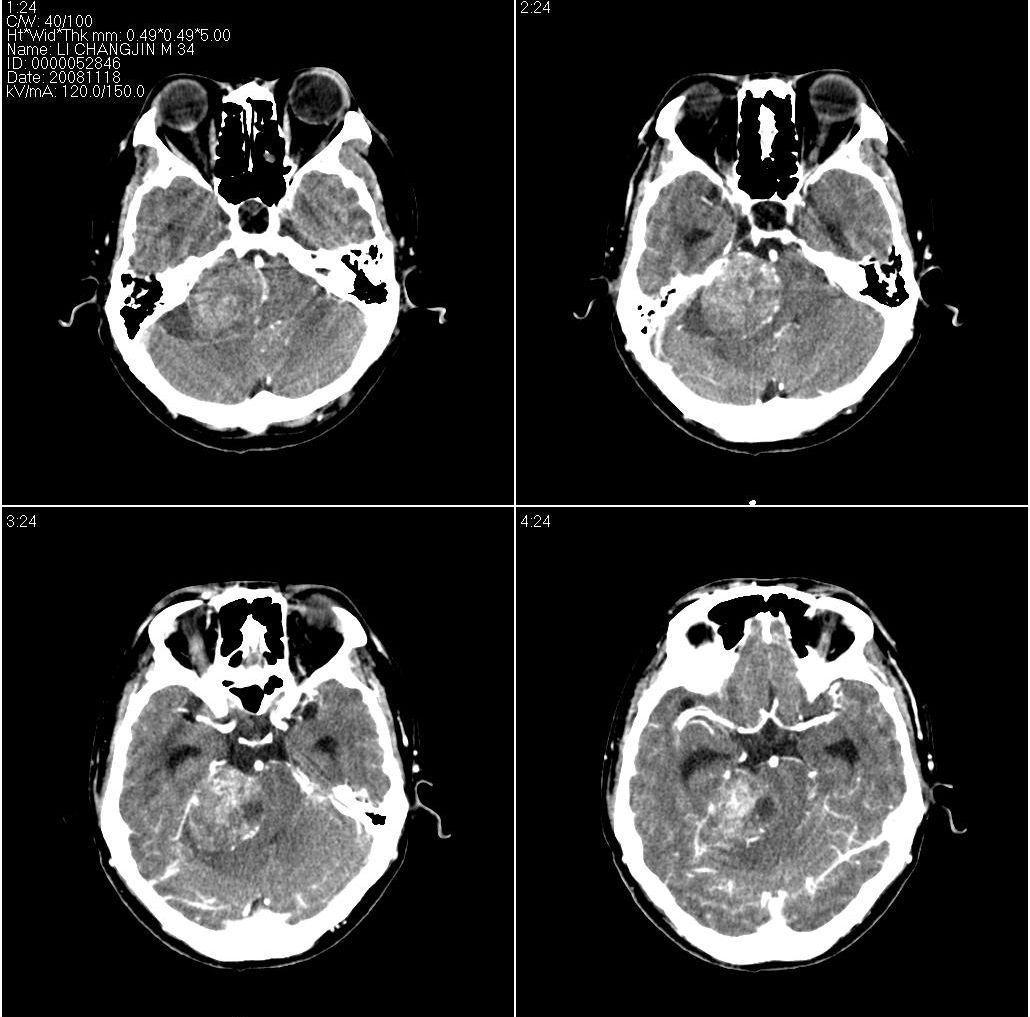

作者: fanshl 时间: 2008-11-20 12:12

标题: 上传增强片,看看到底是什么肿瘤:

[本贴已被 fanshl 于 2008-11-20 4:13:58 修改过]